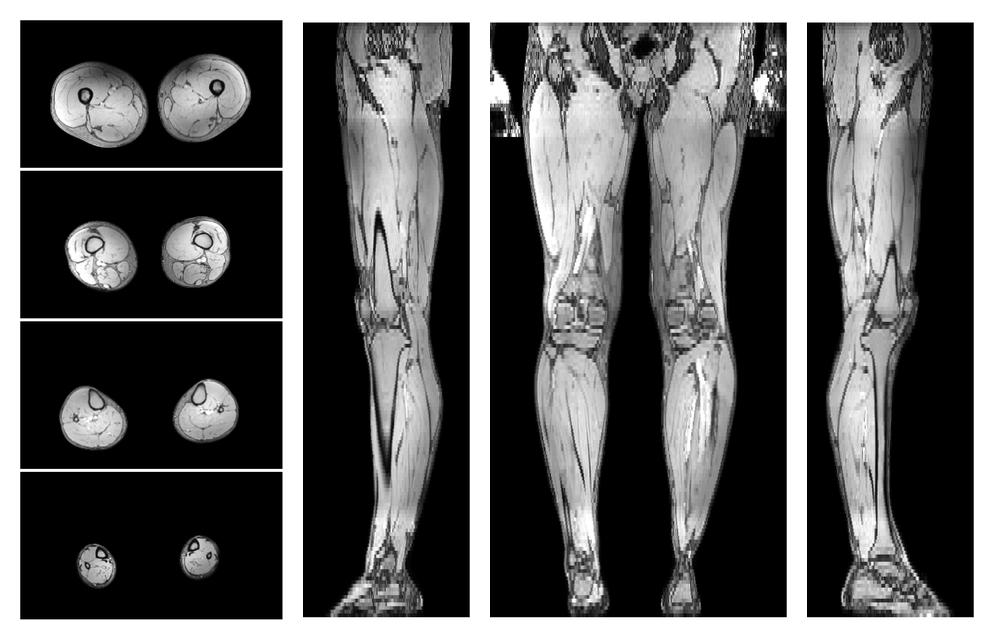

• Automated muscle and bone segmentation.

Overlay of automated muscle segmentation labels on dixon water image.